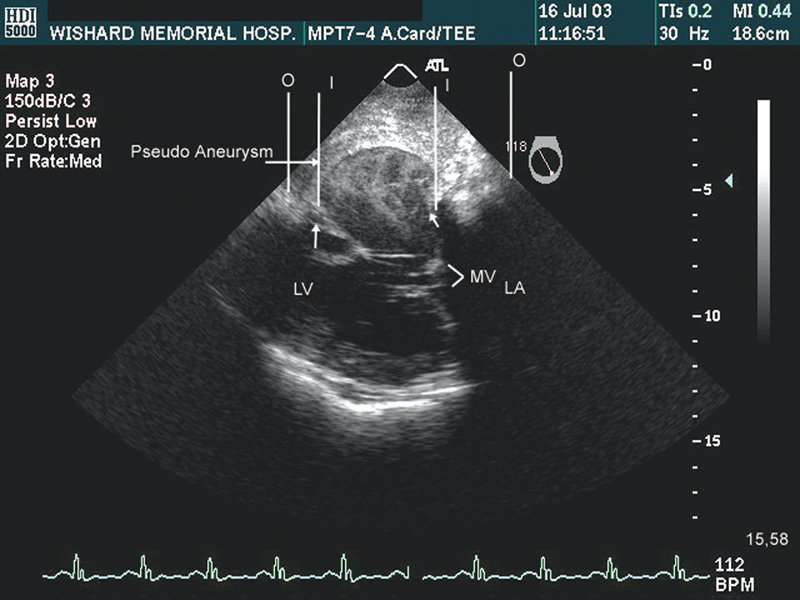

فحوصات تشخيصية لبعض امراض القلب والشرايين التاجية